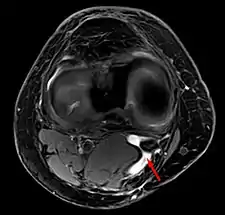

Risk factors include other knee problems such as osteoarthritis, meniscal tears, or rheumatoid arthritis.[1][3][4] The underlying mechanism involves the flow of synovial fluid from the knee joint to the gastrocnemio-semimembranosus bursa, resulting in its expansion.[1] The diagnosis may be confirmed with ultrasound or magnetic resonance imaging (MRI).[3]

Diagnosis is by examination. A Baker's cyst is easier to see from behind with the patient standing with knees fully extended. It is most easily palpated (felt) with the knee partially flexed. Diagnosis is confirmed by ultrasonography, although if needed and there is no suspicion of a popliteal artery aneurysm then aspiration of synovial fluid from the cyst may be undertaken with care. An MRI image can reveal presence of a Baker's cyst.